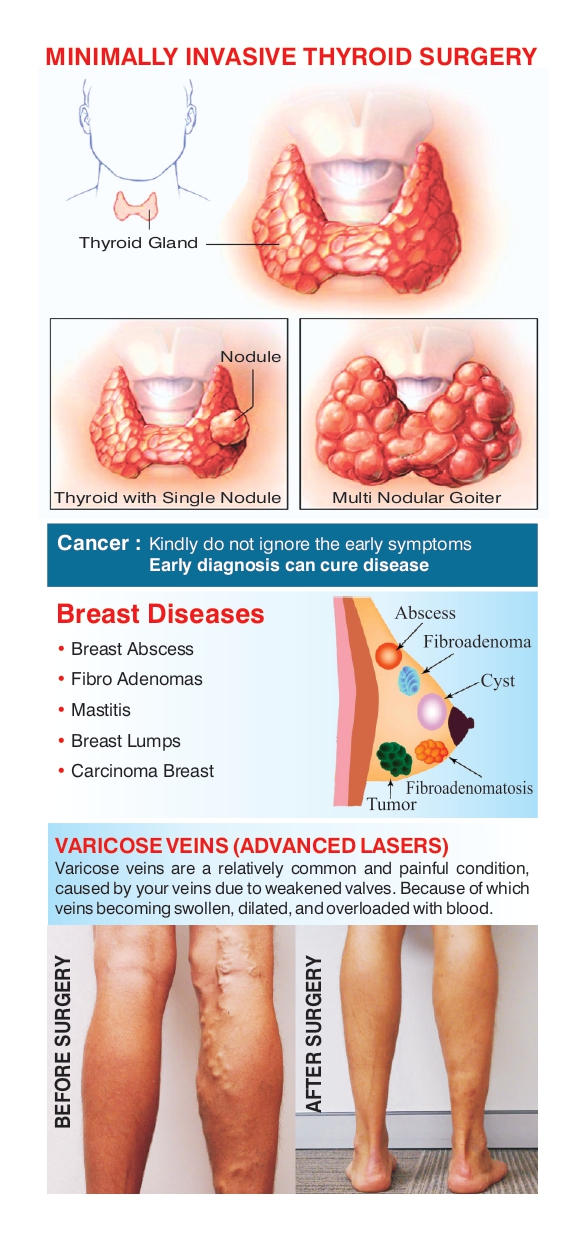

Varicose Veins